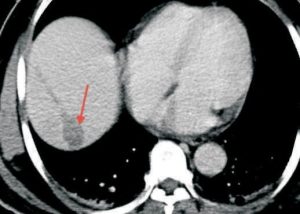

Recently we had an elderly gentleman with a solitary metastatic lesion (Fig. 1) measuring 1.2 cm in diameter in segment 7 of the liver, He had been operated earlier for carcinoma colon. We were able to safely introduce the RFA electrode into the lesion despite its deep location (Fig. 2), without puncturing the overlying pleura and lung, which were in the way. Since the lesion was close to the diaphragm, we had to take care to avoid puncturing the diaphragm. The lesion was ablated at 90 degrees for 7 ½ minutes and a good burn was achieved without any complications (Fig. 3).